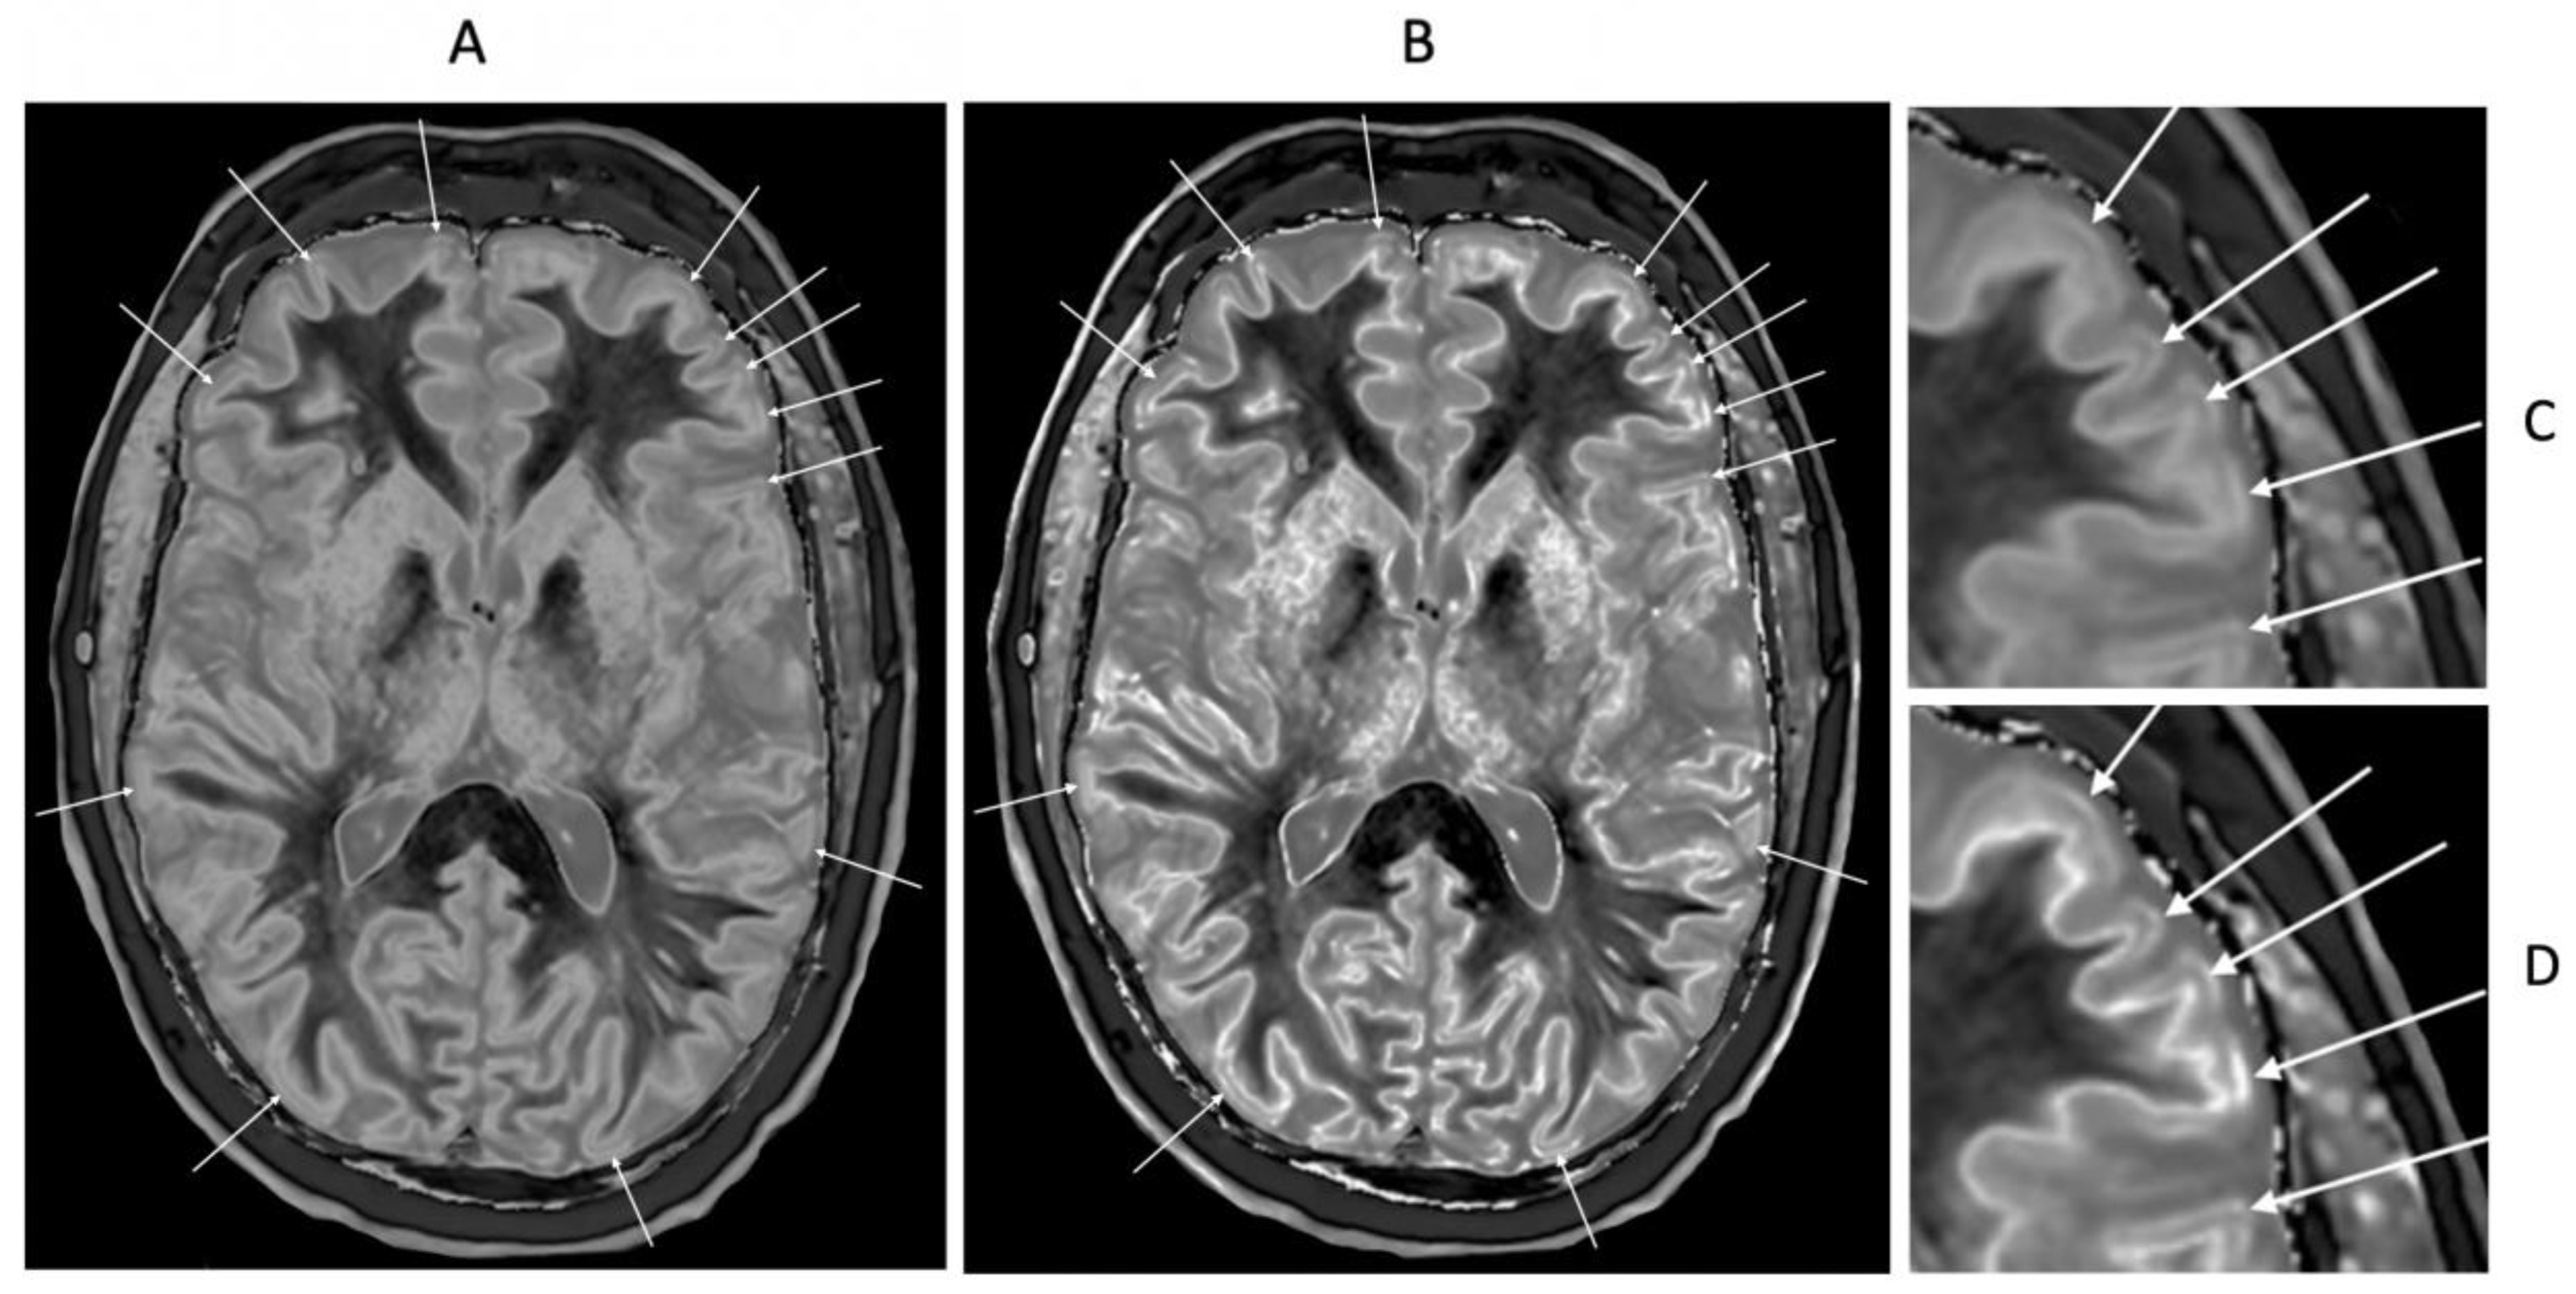

Parkinson’s Disease

Parkinson’s disease may show more obvious bilaminar signs in the cortex than in age matched controls (i.e., an increase in signal in the outer layer of the cortex) with narrow mD dSIR sequences (white arrows) (

Figure 20). The inner higher signal is from the boundary between white matter and gray matter and the next layer outwards is lower signal in the inner cortex. The next outer layer beyond this is the higher signal layer in the outer cortex.

Bubble signs in which circular areas of similar size are seen in the gray matter in the basal ganglia and thalamus can also be seen (e.g., black arrows) (

Figure 20).

Figure 20.

72-year-old male patient with Parkinson’s disease. 2D narrow mD dSIR (T

1-BLAIR) image (A) with insets of anterior left cortex (B) and thalami (C). There is high signal in the superficial layer of the cortex at multiple sites (bilaminar cortex signs) which are more obvious on the inset (white arrows) (B). There are circular appearances in the thalami, putamen and heads of the caudate nuclei (bubble signs) which are more obvious on the inset (e.g., black arrows) (C). The bubble sign is due to focal reductions in T

1 probably from the presence of free iron. The thalamic signal is slightly higher medially compared with laterally unlike the appearance of the normal thalamus in the 18-year-old patient shown in

Figure 12B.

Figure 22.

46-year-old normal control. Narrow mD dSIR (A) and narrow mD lSIR (B) T1-BLAIR images with insets of anterior left cortex dSIR in (C) and anterior left cortex lSIR in (D). The boundaries between white matter and gray matter are seen with higher contrast and the contrast is seen with higher spatial resolution in (B) and (D) compared with (A) and (C). Bilaminar cortex signs are also seen with higher contrast and spatial resolution in (B) and (D) (white arrows). There are also small bubble signs in the putamen and medial thalamus which are better seen on the lSIR image (B) compared with the dSIR image (A).